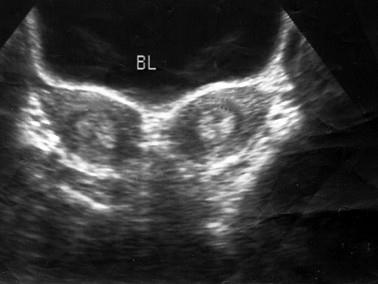

问题 盆腔超声检查如图,最可能的诊断是 ( )

选项 A、畸胎瘤 B、正常声像图 C、双子宫 D、双角子宫 E、幼稚子宫

答案 C